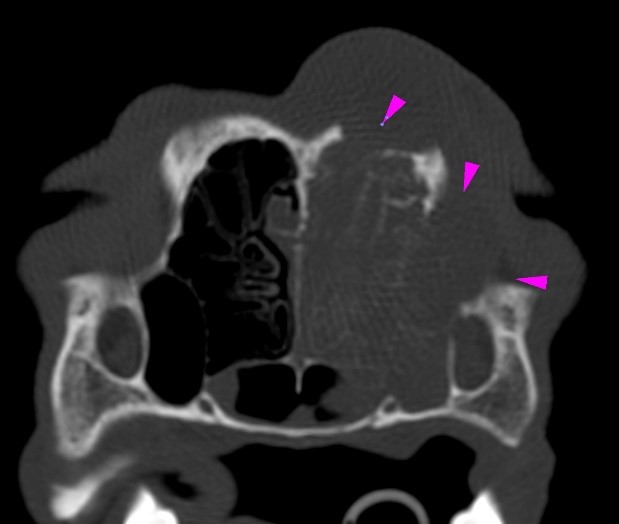

An 11-year-old cocker spaniel was referred to Eastcott Referrals for a chronic nasal discharge and soft tissue swelling in the dorsal aspect of the nose. A CT scan of the head showed a complete obstruction of the left nasal cavity, due to the presence of an amorphous soft tissue mass, extending through the left nasal meatus, left nasal conchae, left sided endoturbinates, left sphenoidal sinus and left frontal sinus (green arrowheads). Bilateral disruption of the turbinates was visible (yellow arrowheads), along with lysis of the left frontomaxillary suture, palatine suture, left rostral portion of the cranium (purple arrowheads) and nasal septum, which was also displaced to the right side